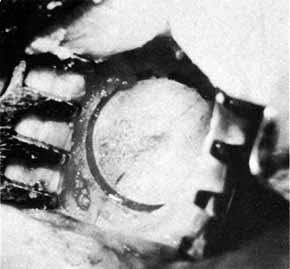

Fig. 33 Granuloma of the punctum secondary to the placement of Silastic tubing. Fig. 33 Granuloma of the punctum secondary to the placement of Silastic tubing.

|

complication of Silastic intubation is the formation of a

granuloma of the punctum or canaliculus (Fig. 33). This problem can be corrected by simple excision of the granuloma